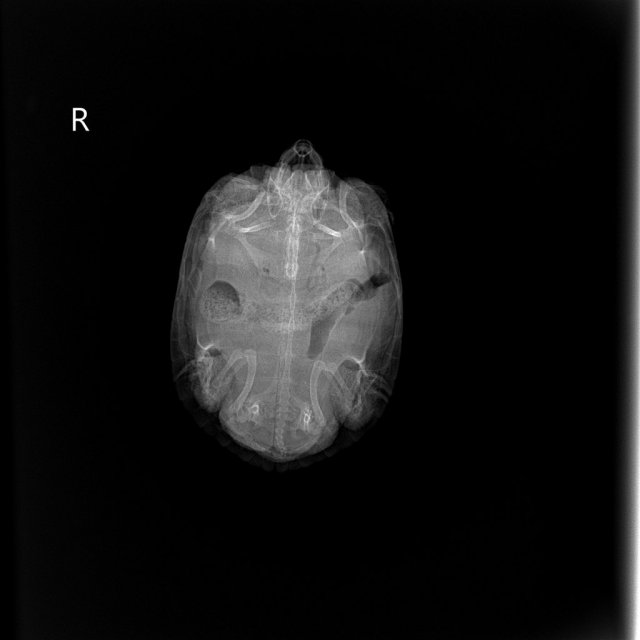

Консультанты moth Ваше имя: Мария Локация: Москва Опубликовано: 8 апреля 2024 Консультанты Опубликовано: 8 апреля 2024 @zfDenis она у Вас когда последний раз какала? по снимкам жкт забит + газы и это всё пережимает лёгкие я ещё нашему врачу скину снимки, чтобы она посмотрела

Консультанты moth Ваше имя: Мария Локация: Москва Опубликовано: 13 апреля 2024 Консультанты Опубликовано: 13 апреля 2024 @zfDenis врач снимки посмотрела и ответила, что по этим снимкам очень сложно сказать пневмония или нет, т.к. очень сильная компрессия из-за забитого жкт. И вялость/слюни/сопли это всё последствия раздувшегося желудка и кишечника. Вам сейчас нужно ежедневно 2 раза в день делать вибротерапию (положить черепаху в небольшой контейнер без воды и поставить на 10 минут на сильно вибрирующий прибор) и затем 20 минут купать в тёплой ванночке с температурой 32 градуса. Не кормить 5 дней. Если за 3-4 дня ситуация никак не изменится/станет хуже - начать колоть антибиотик